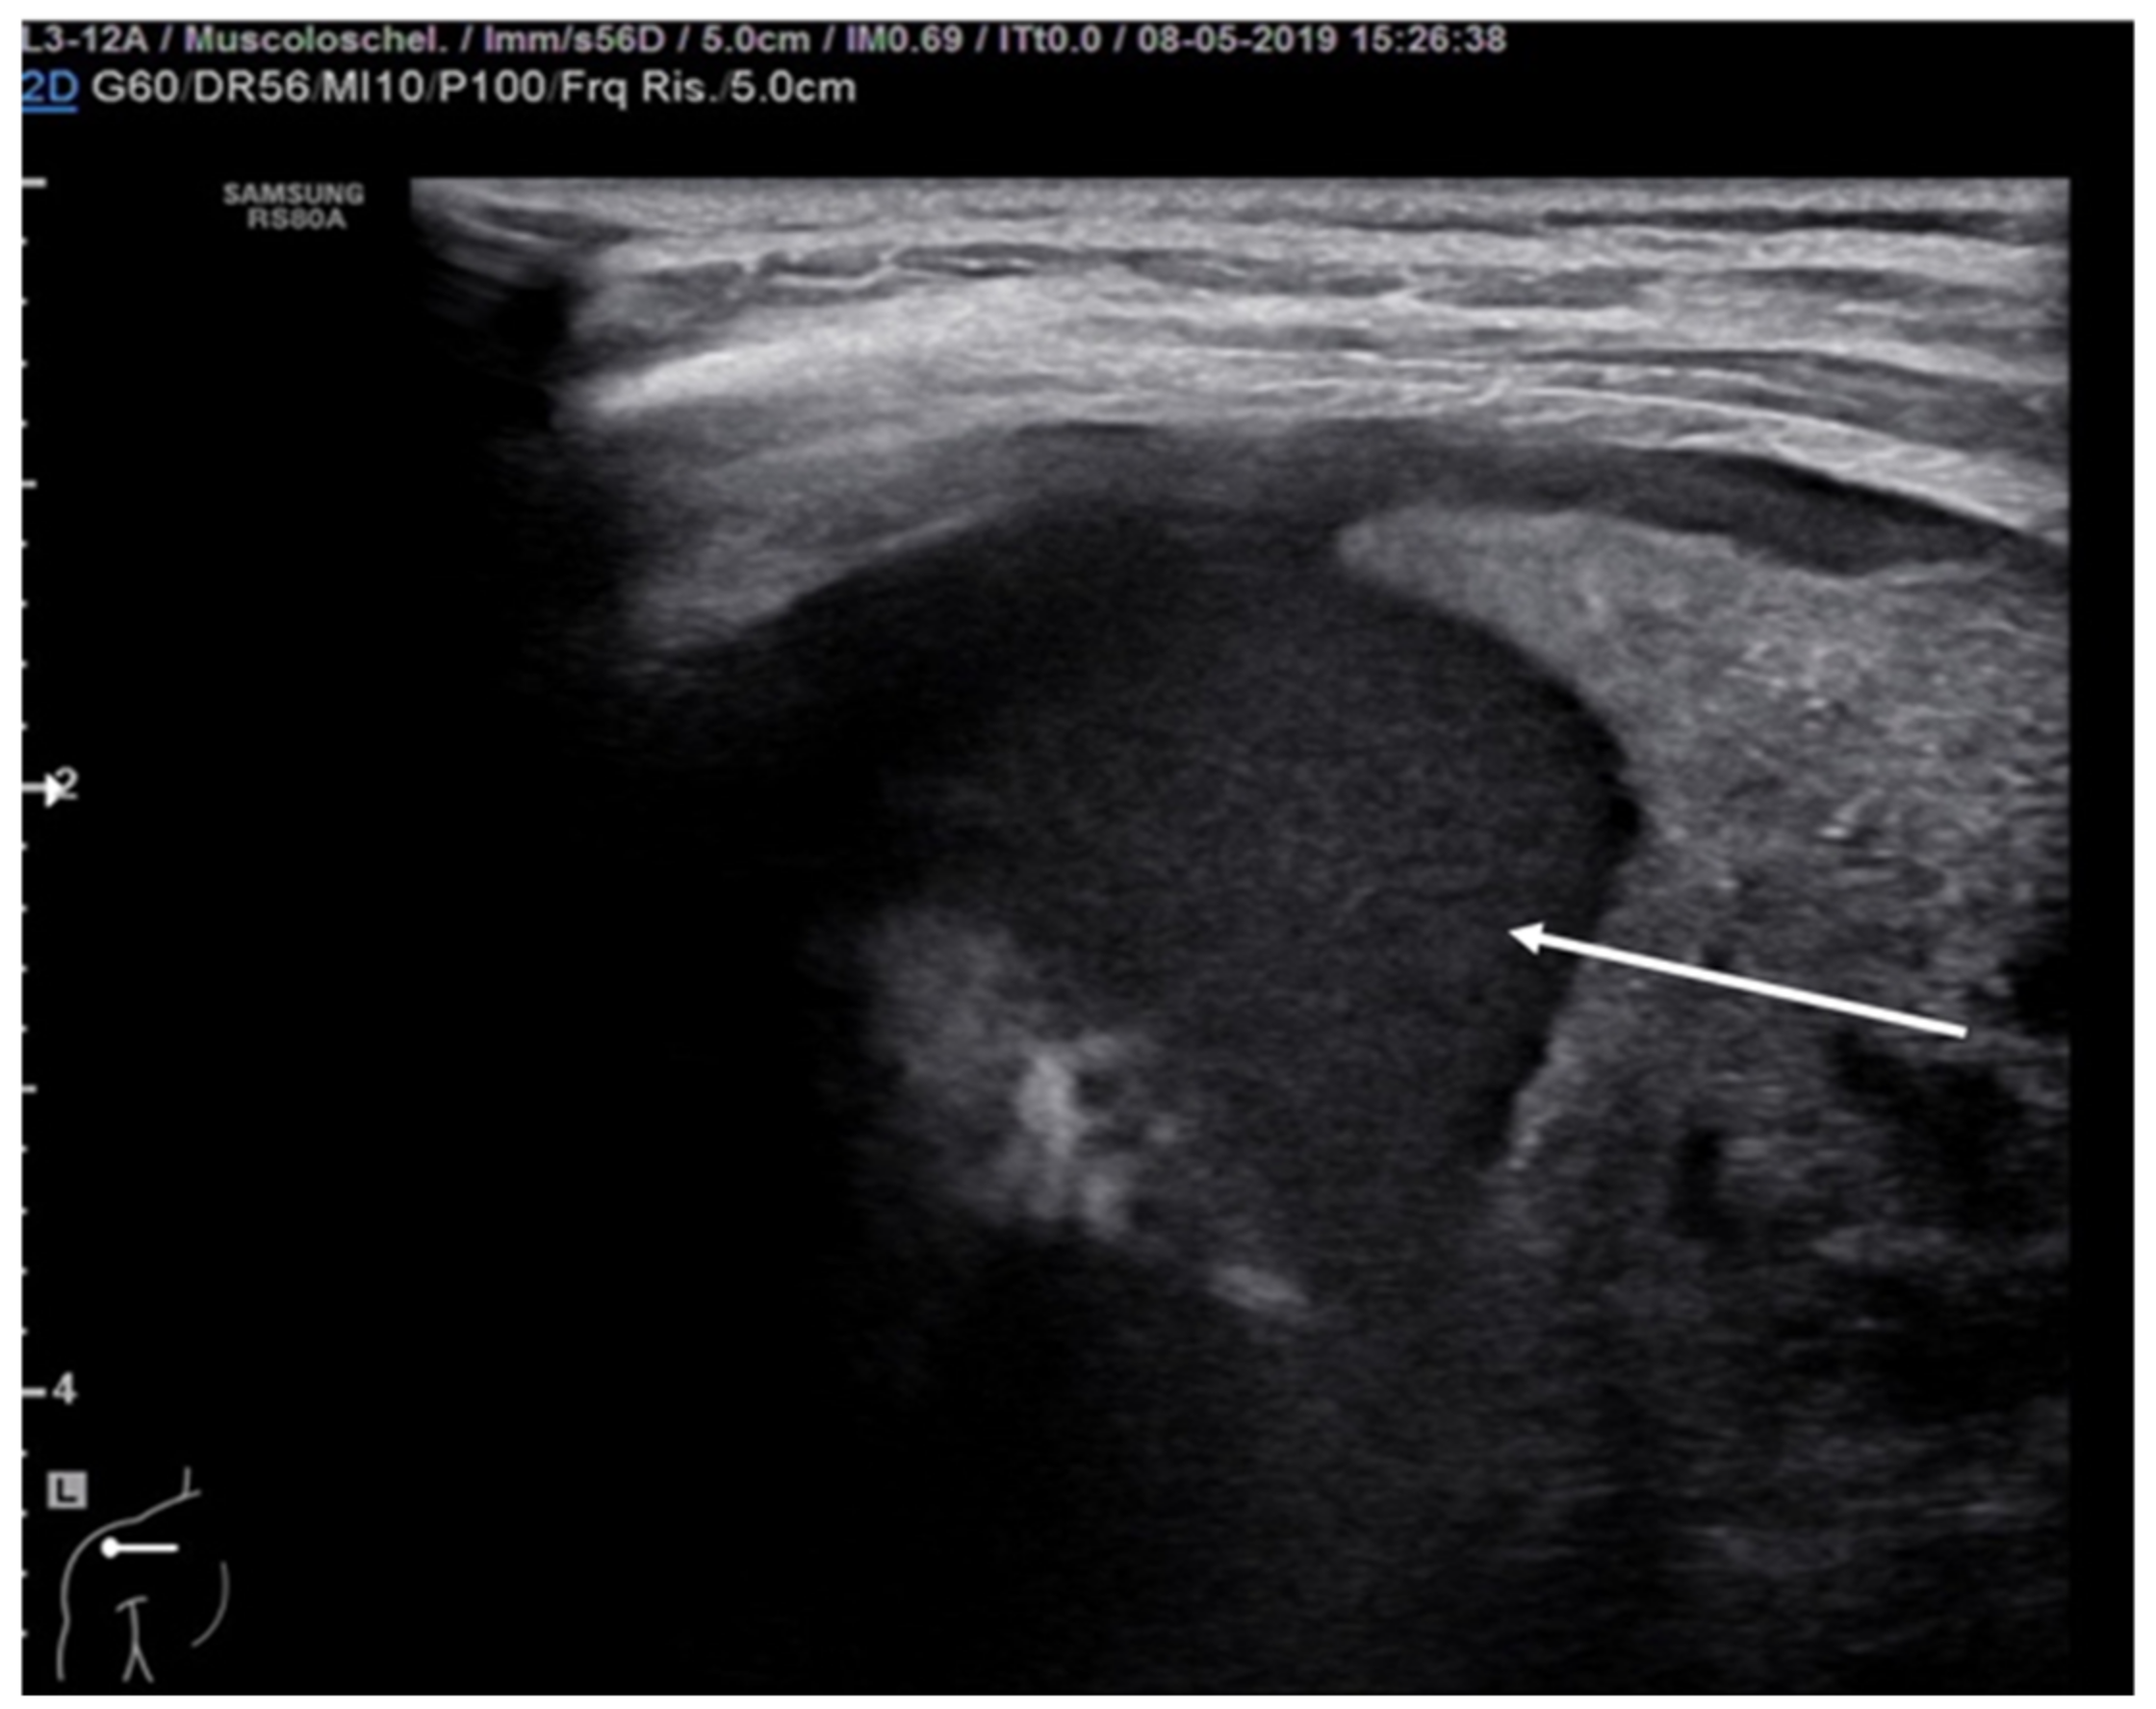

Pleural empyema refers to an infected, purulent and often loculated pleural effusion due to parenchymal infection that spreads to the pleural cavity. Ultrasound examination of the chest revealed a hypoechoic lesion with complex-septated effusions, passive atelectasis, width uniformity and smooth luminal and outer margins (Figure 12). Color Doppler can be used to differentiate the peripheral air-fluid abscess from empyema. In fact, color Doppler ultrasound vessel signals in pericavitary consolidation are a predictor of lung abscess [57,58,59,60].

Figure 12.

Hypoechogenic and highly corpuscular collection suggestive of pleural empyema (white arrow).